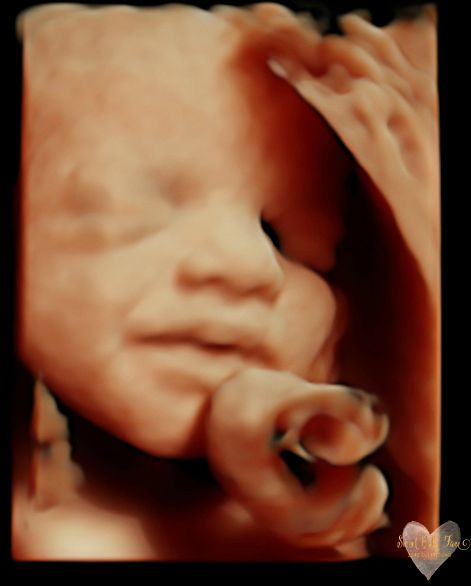

3D/4D/5D Ultrasound Gallery

Take a peek at our Photo Gallery. All of our 2D, 3D, 4D, HD elective ultrasound images are truly ours. They come directly off our machine from our highly trained staff. We can start getting great 3D/4D images as early as 10 weeks!